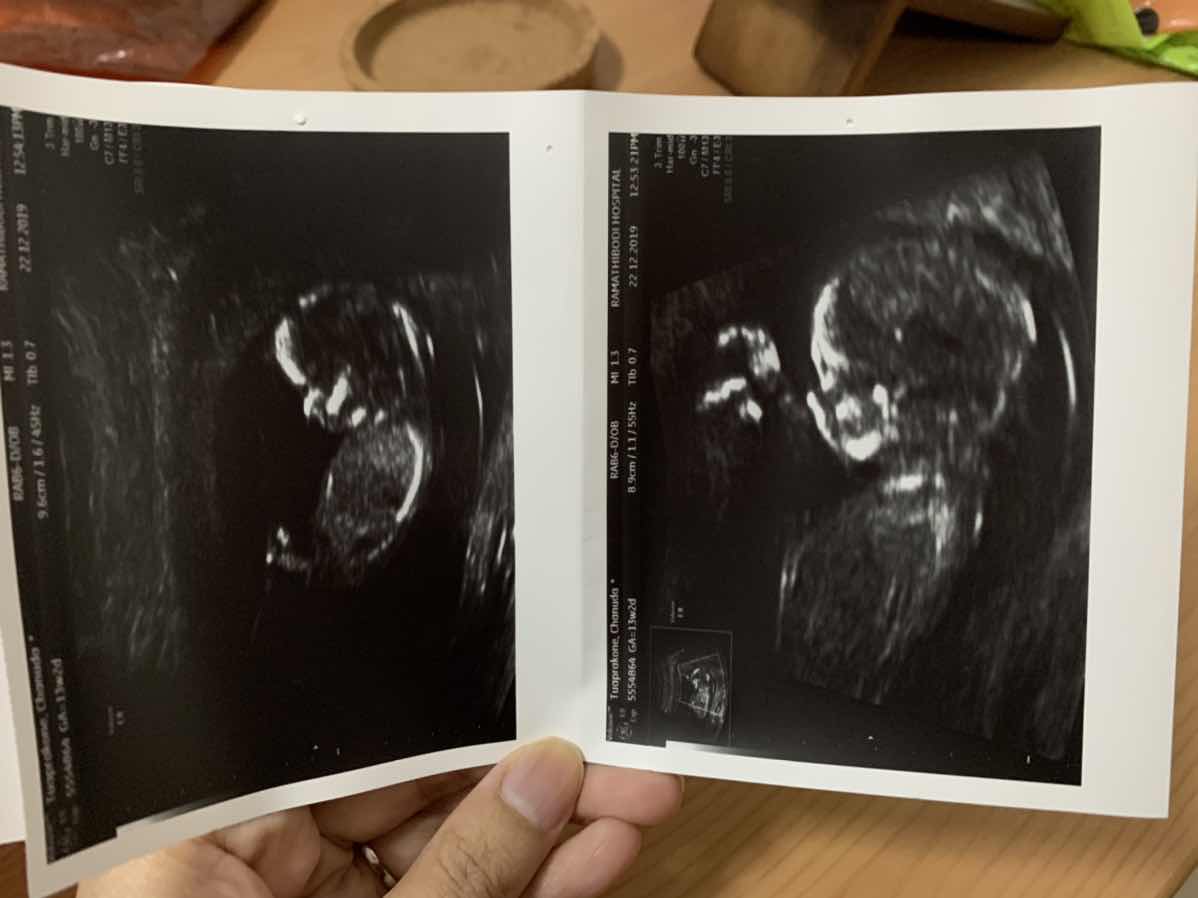

ตอน 15 w จ้าา